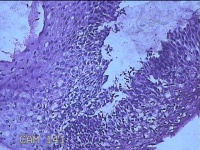

宫颈7点组织

性别

女

年龄

35岁

临床诊断

子宫颈上皮瘤样病变

一般病史

宫颈高危HPV18感染。

标本名称

大体所见

灰白粉红色不规则碎组织0.8x0.5x0.3cm一堆。